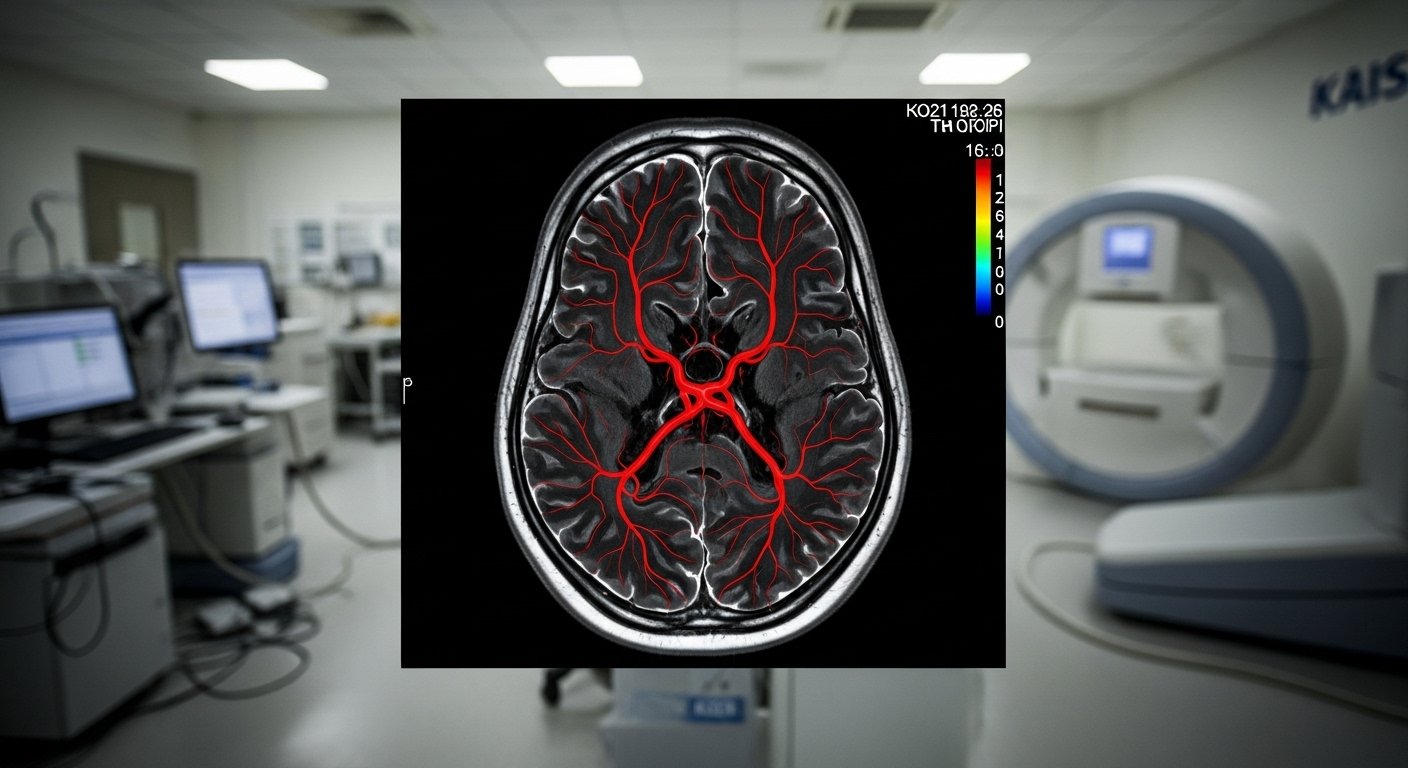

KAIST 바이오및뇌공학과 박성홍 교수 연구실은 최근 열린 'MICCAI 톱브레인 챌린지'에서 MRI와 CT 뇌 혈관 영상 두 부문 모두에서 1등 상을 수상했습니다. 이 대회는 뇌 혈관의 지도를 얼마나 정확하게 그리는지를 두고 전 세계 AI 전문가들이 실력을 겨루는 가장 권위 있는 대회 중 하나입니다.

이 기술은 우리의 삶과 건강에 직접적인 도움을 줄 수 있습니다. 뇌졸중이나 뇌동맥류처럼 터지기 전까지 알기 어려운 '뇌 속 시한폭탄' 같은 질병을 조기에 발견할 가능성을 크게 높입니다. 의사들이 AI가 그려준 정밀한 뇌 혈관 지도를 보고 병의 위치와 상태를 훨씬 빠르고 정확하게 파악할 수 있게 됩니다. 이는 환자 맞춤형 치료 계획을 세우는 정밀 의료 시대를 앞당기는 중요한 발걸음이 될 것입니다.앞으로 뇌 질환 정복도 가능할까?